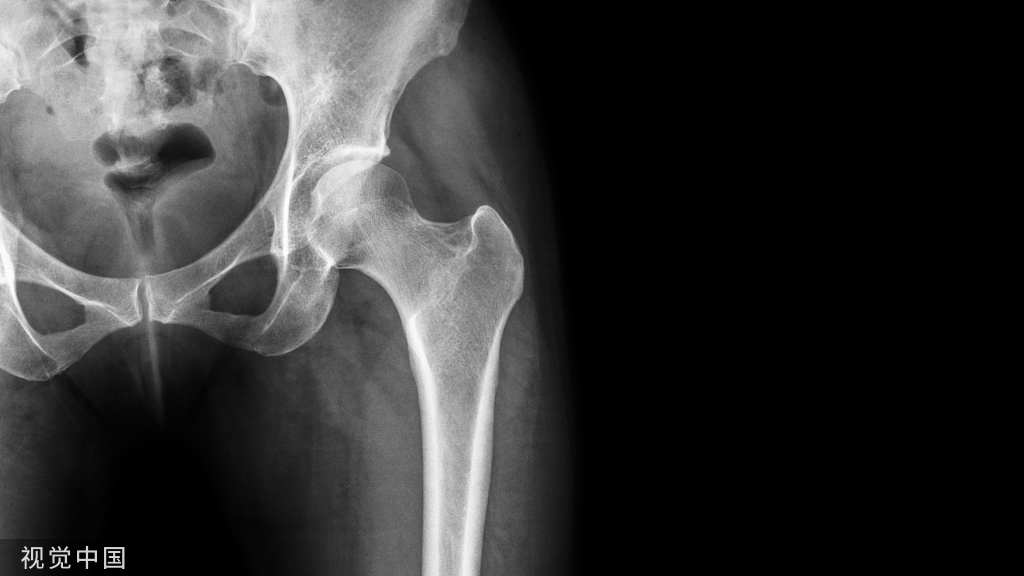

下颌骨由下颌体和下颌支两部分组成,呈马蹄形。下颌体分为内面、外面、牙槽突和下颌体下缘。

下颌支由喙突、髁突、内、外面四部分组成。下颌骨牙槽突的内侧骨板和外侧骨板都由骨密质构成,骨松质被内外侧骨板包绕其中(图1~3)。